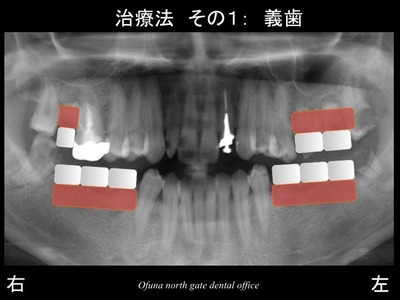

先程の×印を抜歯した場合には、以下の2つの治療方法が考えられます。

まず、義歯(入れ歯)です。

次にインプラント治療です。

患者様は、取り外し式の義歯(入れ歯)はご希望されませんでした。

固定式であるインプラント治療を希望されました。